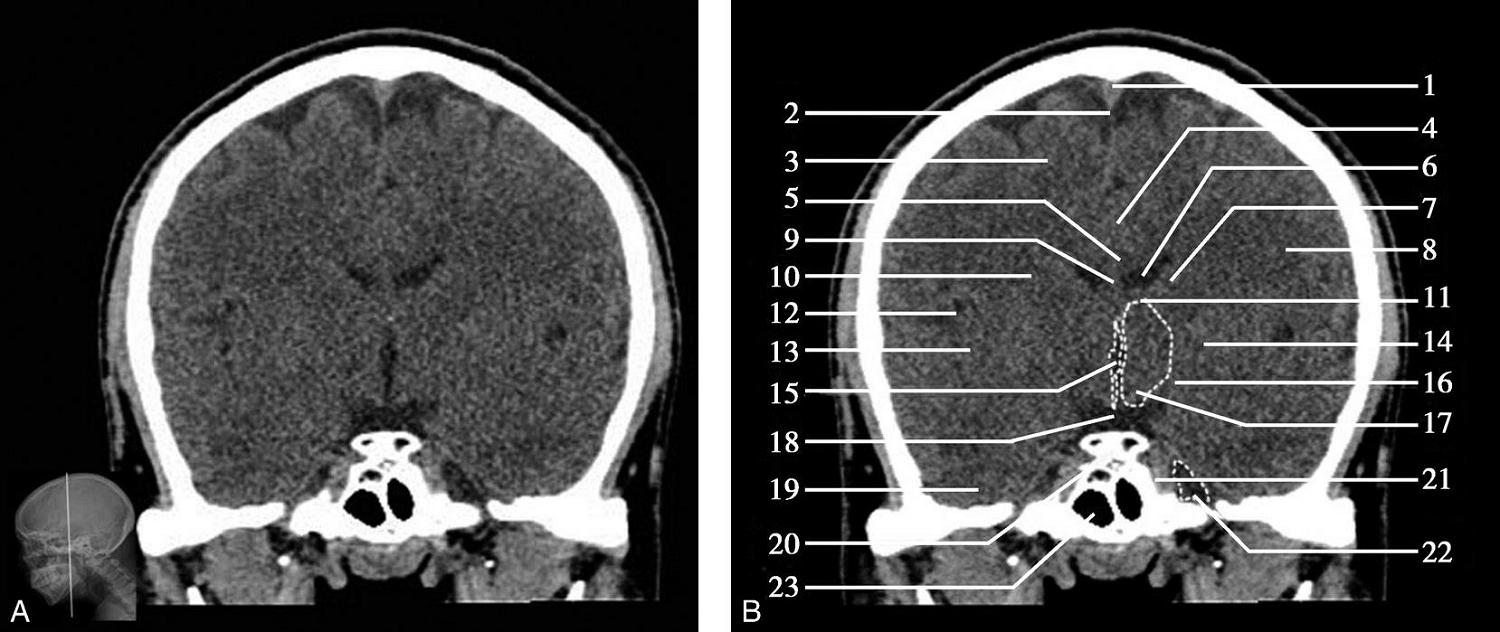

重要结构:卵圆孔、棘孔、破裂孔、斜坡、颞骨岩部、颈静脉孔(图1-2-1、图1-2-2)。

图1-2-1 颅底层面

A.横断面;B.横断面标注

1.晶状体;2.筛窦;3.颞肌;4.中颅窝底;5.外耳道;6.延髓;7.乙状窦;8.小脑半球;9.眼球;10.眼眶;11.上颌窦;12.蝶窦;13.乳突;14.耳郭;15.小脑蚓部;16.枕内隆凸

图1-2-2 颅底层面(骨窗)

1.鼻骨;2.筛窦纸板;3.颧骨眶突;4.翼腭窝;5.蝶骨大翼;6.卵圆孔;7.破裂孔;8.颞骨颧突;9.棘孔;10.斜坡;11.颞骨岩部;12.乳突;13.颈静脉孔;14.枕乳突缝;15.枕骨;16.枕内隆凸

层面前部呈开口向前的“V”字形,正中为鼻中隔,向两侧依次为筛窦和眼眶,眼眶内前部为眼球,后部为眶脂体。翼腭窝位于眼眶后部,窝内含有脂肪并有上颌神经通过。层面中部为蝶骨体,蝶骨体中部可见含气蝶窦,蝶窦后方为枕骨基底部,两者呈前后关系,其上面构成斜坡。蝶窦两侧为蝶骨大翼,其后外侧缘处由前向后可见卵圆孔和棘孔,分别有下颌神经和脑膜中动脉通过。斜坡外侧、岩骨尖前方为破裂孔。蝶骨大翼与眶外侧壁的颧骨借颧弓相连,颧弓和蝶骨大翼之间有咬肌及颞肌。层面中部外侧为外耳道。颞骨岩部呈“八”字形,相互之间借破裂孔软骨、蝶岩软骨结合和岩枕软骨结合连接。岩部后外侧的乳突部内可见乳突小房,乳突部与枕骨相接。岩骨后部可见颈静脉孔,内有颈内静脉、舌咽神经、迷走神经和副神经通过。层面后部为颅后窝,其内可见延髓,延髓前方为延髓前池,内有椎动脉,后外侧为小脑半球下部,后方为第四脑室、小脑扁桃体及小脑蚓部。

破裂孔、卵圆孔、棘孔及斜坡等均为重要的解剖结构,临床常见疾病如鼻咽癌常侵犯上述结构(图1-2-3)。颈静脉孔区较常见的肿瘤为颈静脉球瘤,常伴有颈静脉孔及其邻近骨质的破坏(图1-2-4)。